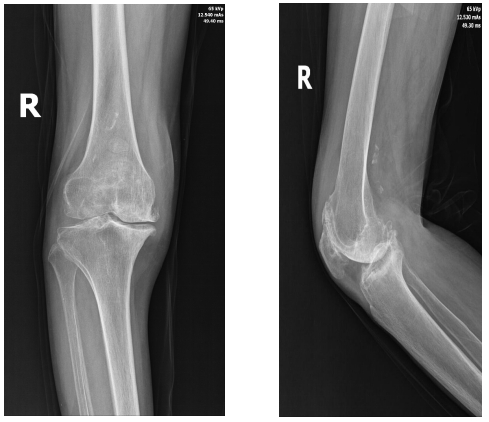

患者82岁,因双膝关节疼痛20余年到我院就诊,左膝疼痛评分7分,右膝疼痛评分8分,入院后查体:O型腿,双侧膝关节屈伸活动受限,压痛明显,以双侧膝关节内下为甚,又以右侧为甚,DR检查双侧膝关节骨性关节炎。